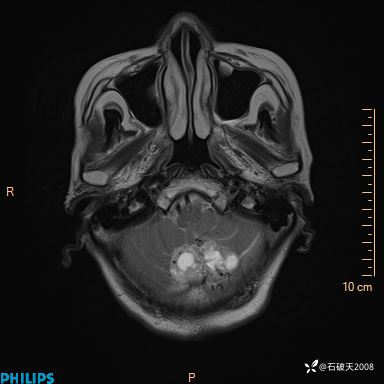

书上说这个肿瘤发生在幕下仅4.09%,你会想到它吗?(病理已公布)

女 86岁 主 诉:乏力1月

现病史:患者1月前活动出现双下肢乏力,无头晕、头痛、恶心、呕吐、肢体活动不利,休息后缓解,间断断发作,症状进行性加重,在家口服药物治疗(具体不详),效差,为进一步诊治,来我院,门诊按“乏力”收住我科,患者自发病以来,神志清,精神稍差,饮食睡眠欠佳,大小便正常,体重未见明显改变。

T2